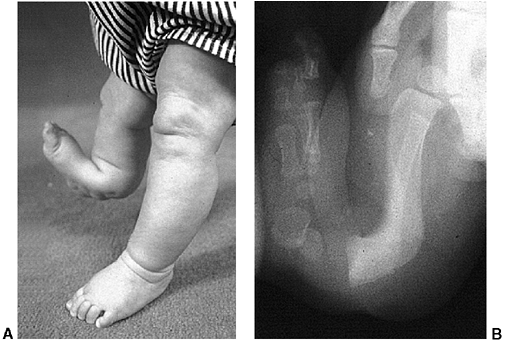

![]() |

|

Figure 28.4 A: Internal tibial torsion is often seen in toddlers in association with physiologic bowlegs and results in an in-toed gait. B: The thigh-foot angle is best assessed in the prone position.